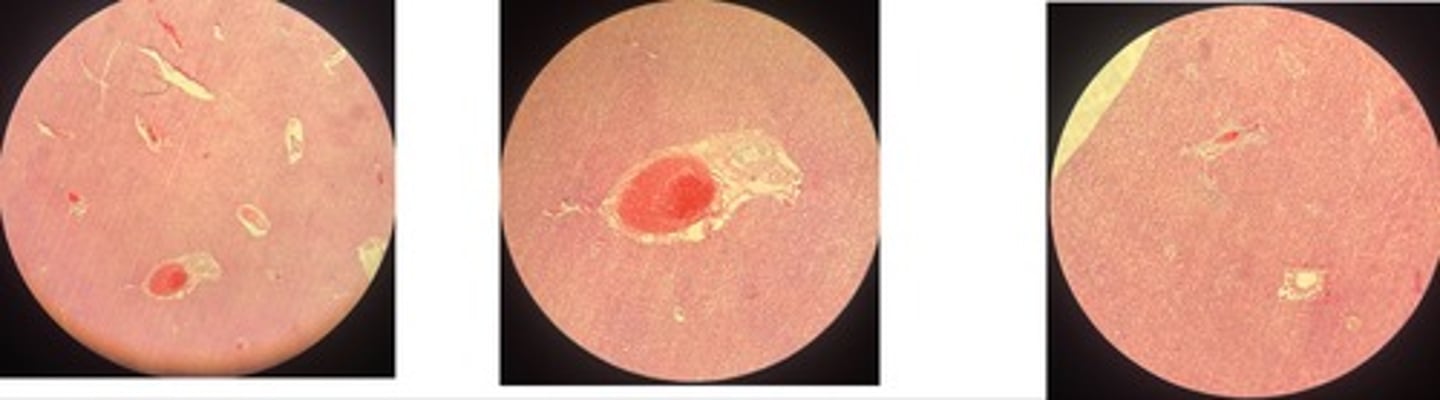

Pulmonary tuberculosis

- central necrosis surrounded by epitheloid cells w/ giant cells btw

- infiltrates of lymphocytes, plasma, fibrosis